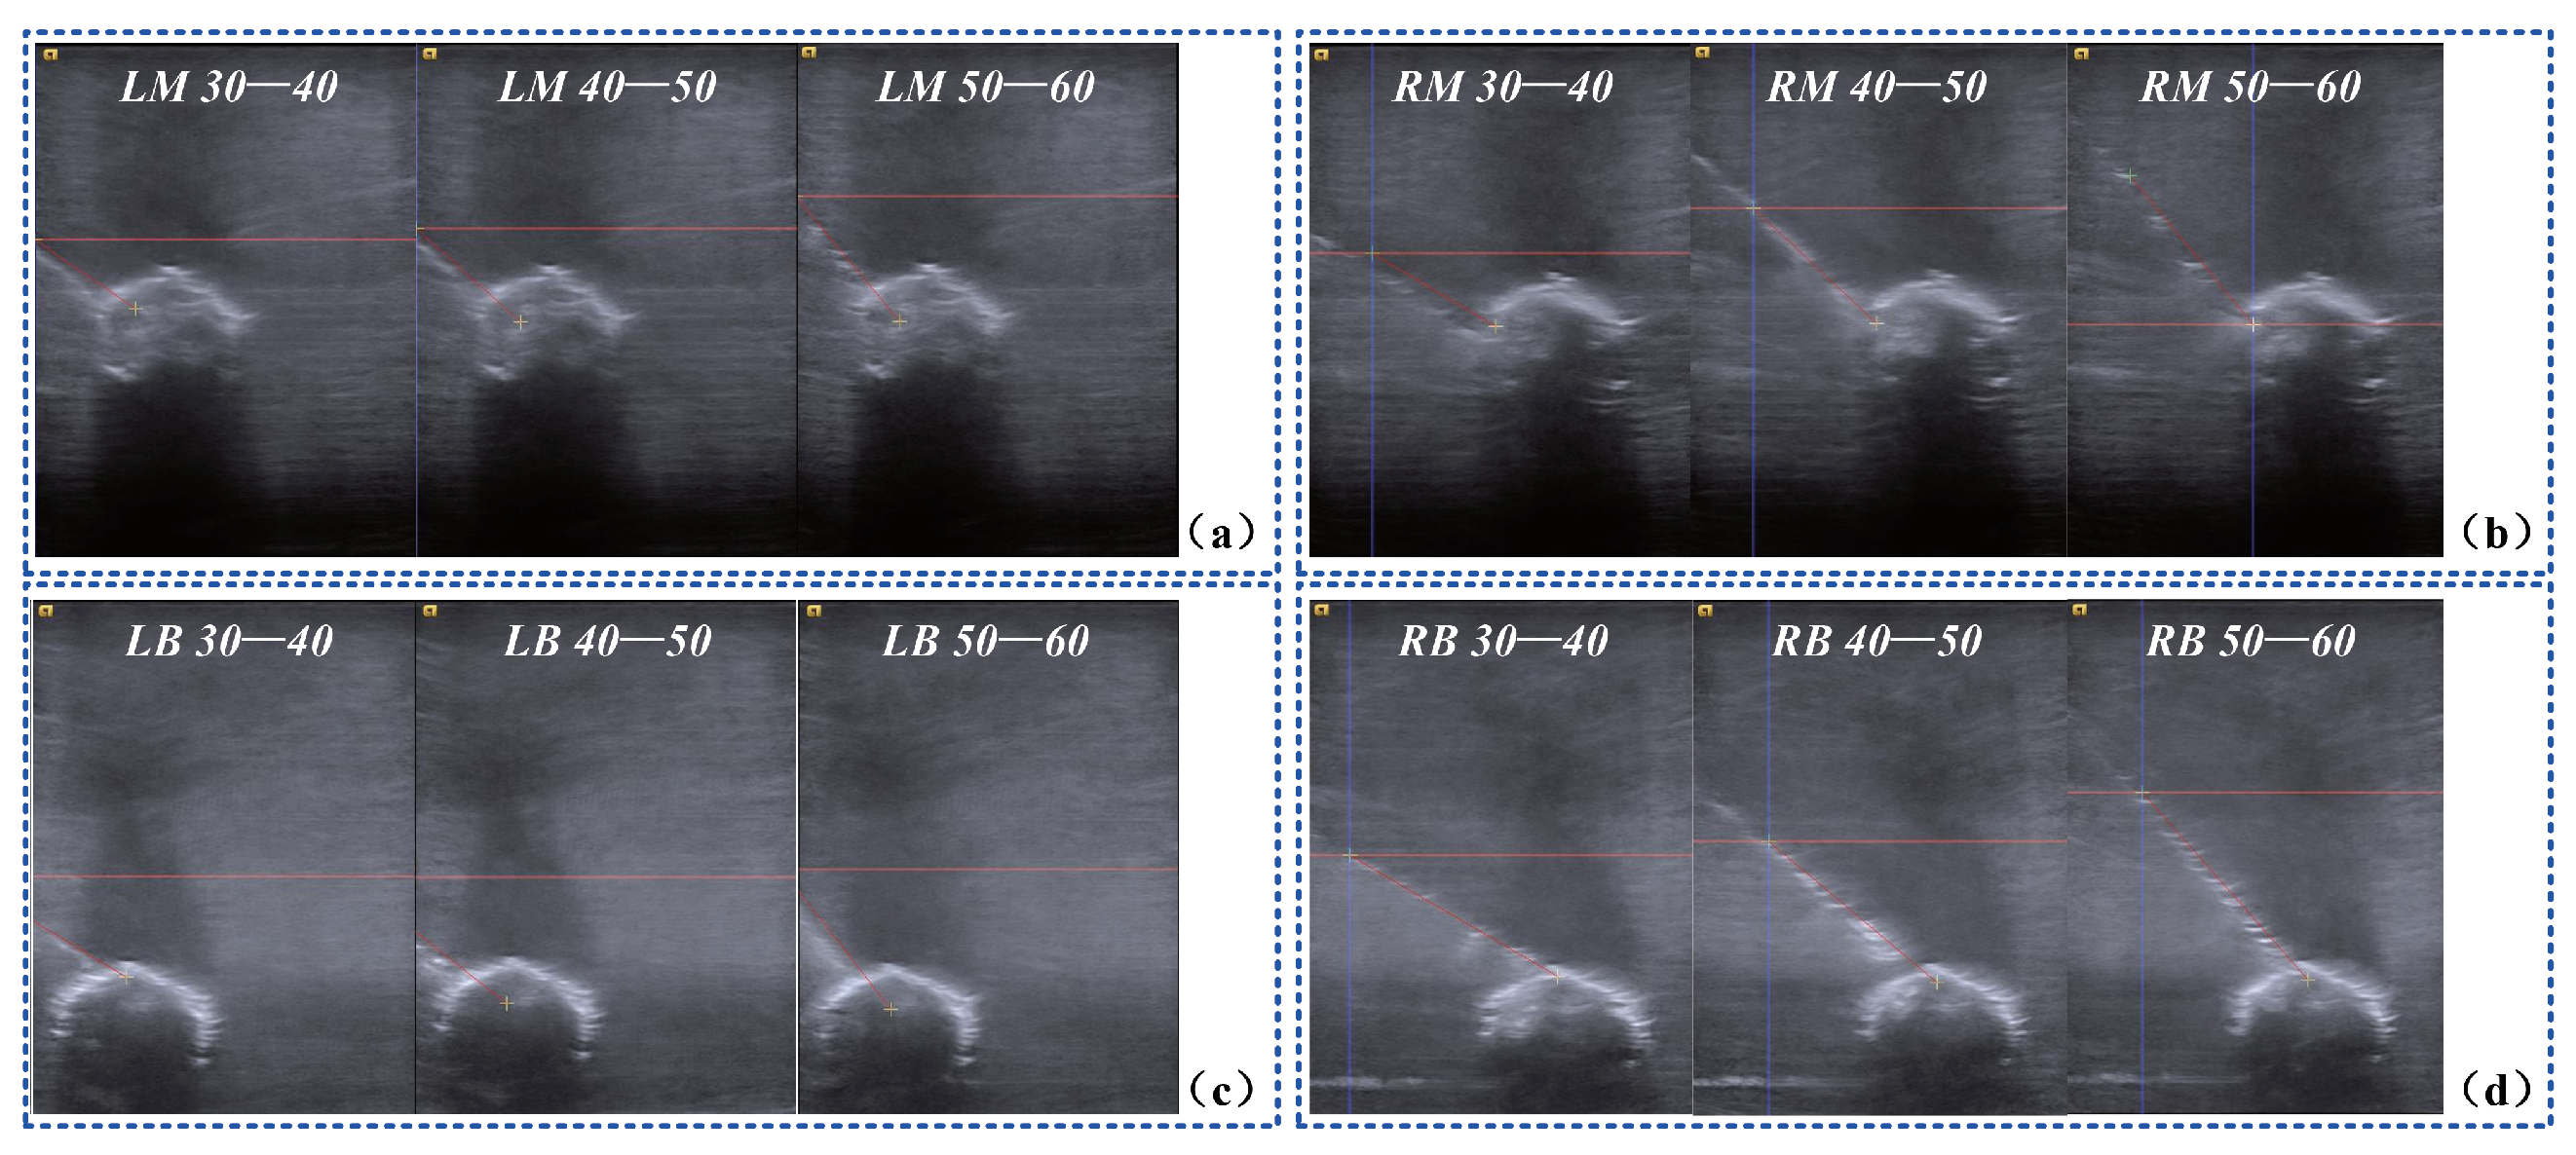

4.4. Blueberry Biopsy Experiments

We designed biopsy experiments on a blueberry submerged in a water tank as shown in Figure 10. The target blueberry had a size of ϕ 14.5 mm ×   9.6 mm, and a biopsy needle had a diameter of 0.8 mm. We divided the water tank into 3 × 2 blocks and fixed the blueberry in the lower four blocks to simulate deep seated lesions. Moreover, the incline angle of the planned trajectory was varied over the range 30 to 60 . The biopsy path can be real-time tracked by the ultrasound system. Thus, the biopsy accuracy was quantified by path deviations.

As shown in Figure 13, we quantified the deviations of the targets and the trajectories when the blueberry was submerged in different blocks of the water tank. The experimental results of the 72 times biopsy on a blueberry are presented in Table 4. An average distance error of 0.74 mm and an average angular error of 1 . 10 were founded. Throughout the 72 times biopsy, the successful rate was 100 % .

Figure 13. US images of the biopsy on a blueberry. (a) biopsy on the targets in the left middle block from three different angles; (b) biopsy on the targets in the right middle block from three different angles; (c) biopsy on the targets in the left bottom block from three different angles; (d) biopsy on the targets in the right bottom block from three different angles.